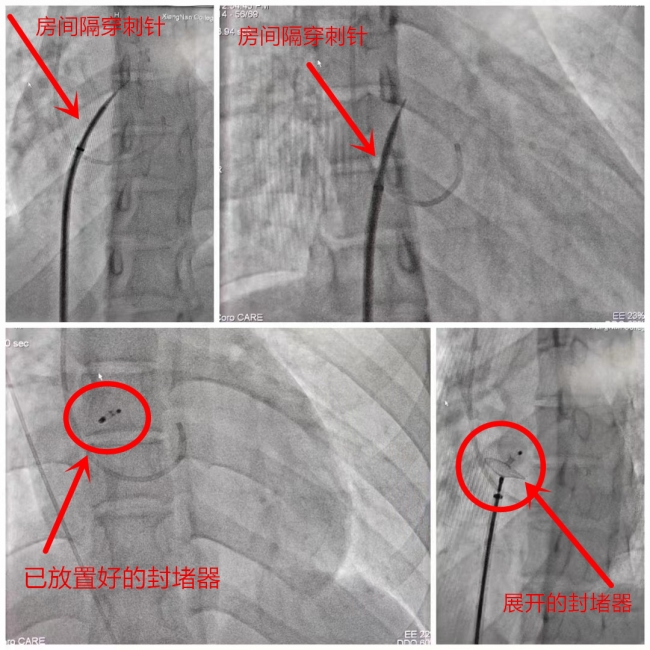

李维军介绍说,“相比于传统的外科修补术,介入封堵术是一种微创手术,不用开刀,医生通过穿刺大腿根部的股静脉,将一根导丝沿着血管走形送入心脏右心房,穿过未闭卵圆孔至左心房,释放封堵器进而永久性关闭卵圆孔。这种手术方式,创伤小,并发症少,术后第二天患者就可以自行下床活动。” 6月2日,李维军团队成功完成了卵圆孔封堵手术。困扰小李多年的疾病终于得以解决。